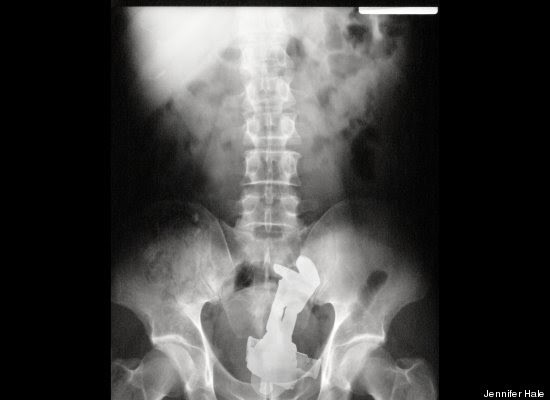

"Stack Up!" es una muy divertida colección de 100 imágenes de rayos X que muestra cuerpos extraños ingeridos o insertados en el cuerpo humano, tanto por accidente o de forma voluntaria, aunque se haga difícil imaginar el motivo de algunas de tales inserciones.

Los autores del libro -dos psiquiatras y un médico de sala de emergencias- aseguran -sin mucha originalidad pero con conocimiento de causa, que la imaginación humana no tiene límites. Esta afirmación es aplicable tanto a la calidad y variedad de objetos tragados o incorporados al cuerpo, como a los motivos o excusas utilizados para justificar la presencia de dichos objetos.

"Hay gente que hace cosas realmente imprudentes, y luego trata de racionalizarlas", advierten los autores en la solapa del libro, destacando precisamente la imaginación humana para "dar con usos imprevistos para objetos de la vida cotidiana".

"Tenía las manos ocupadas", "me caí encima", son algunas de las excusas que los profesionales de la salud escuchan de los pacientes que llegan a los hospitales con "cuerpos extraños extrañamente metidos en el cuerpo".

Redactado de manera humorística, el libro se pregunta cómo un teléfono celular puede haber ido a parar al sitio de la anatomía del propietario donde nunca da el sol, respondiéndose que, probablemente, estuviera en modo vibrador.

"Hallar un termómetro atascado en el recto de un adulto puede resultar corriente. Pero ¿Qué se puede decir de una muñeca Barbie, perteneciente a su hija de seis años?", se preguntan los autores, añadiendo el consejo infaltable: no hagan esto en casa.